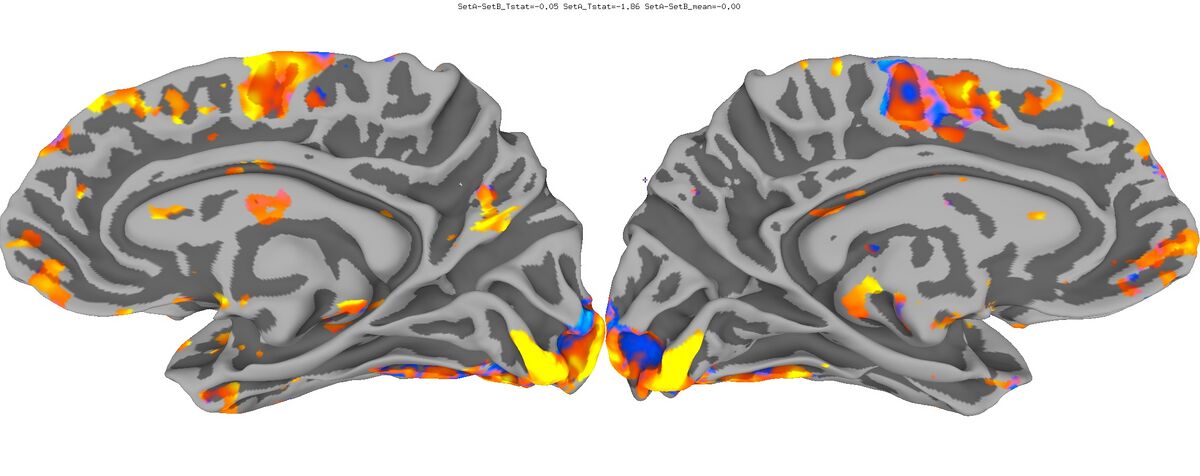

Functional Data

Functional data of the Mouth vs. Eye contrast mapped to the average surface. It is hard to quantify the difference, but one way is to compare the maximum statistical values; with better intersubject alignment, these would presumably increase.

1. NEW: Max t-value for Mouth: 9.3 Eye:10.1 Eye vs Mouth: 5.6

2. OLD: Max t-value for Mouth: 7.9 Eye:8.8 Eye vs Mouth: 5.8

Old